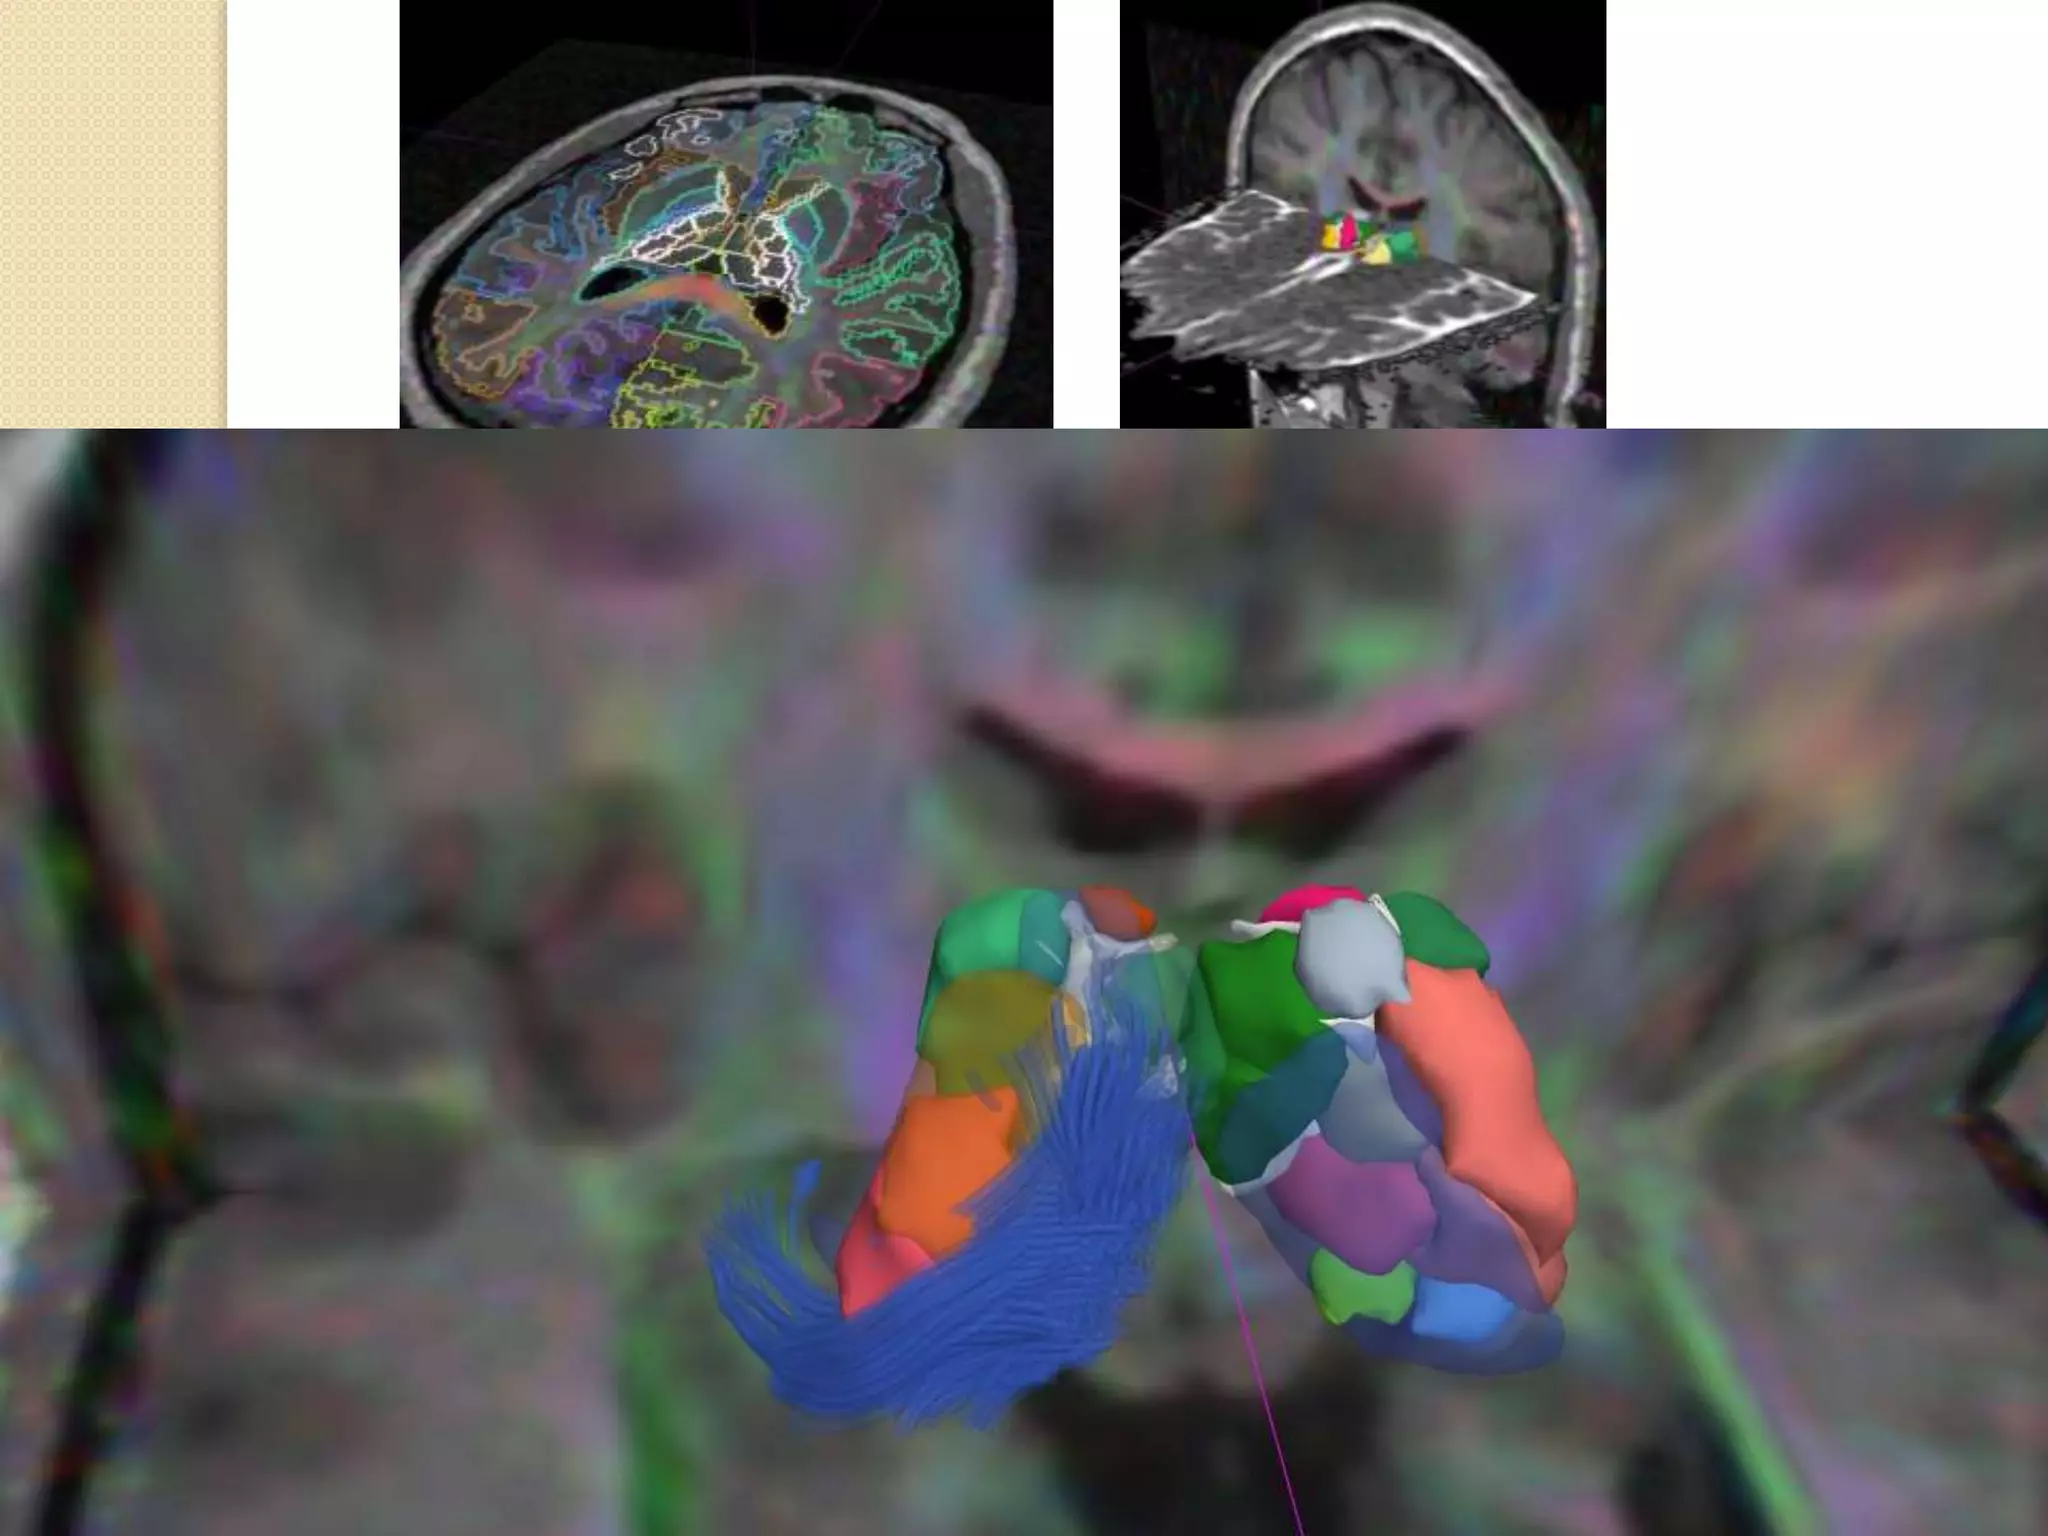

Diffúziós traktográfia

 Diffúziós tenzor adatok alapján a fehérállományi pályák

háromdimenziós megjelenítése

 Agyi összeköttetések (?)

 Számítógépes adatfeldolgozás és megjelenítés

Diffúziós traktográfia: példák

 Tractus corticospinalis megjelenítése

 Egyéb pályák megjelenítése

Konnektivity (c) Jakab A.

DTI és a multimodalitás

 DTI és más, pl. strukturális MRI képek együttes megjelenítése

 Térbeli illesztés, koregisztráció szükséges

 TÖBBLETINFORMÁCIÓ: fehérállományi képletek